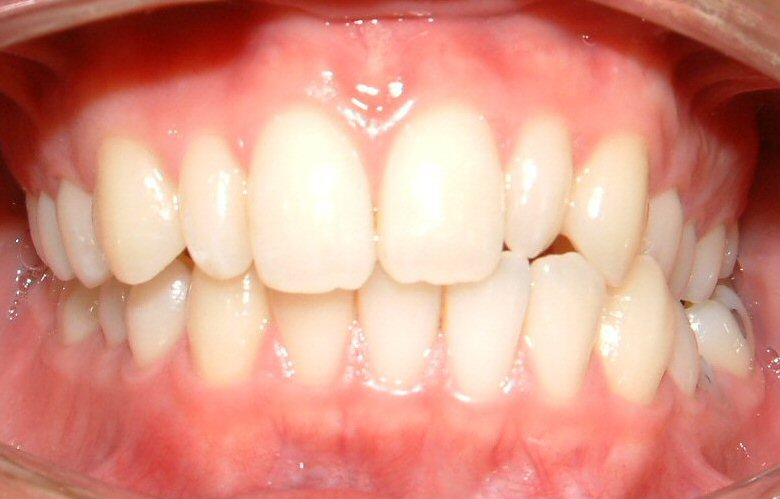

Figs. 1-7 are used with the intention of showing a case that requires a TAD. Not all orthodontic cases need TADs. The upper midline is coincident with the facial midline (not shown), but the lower midline is shifted to the patient's left about 4 mm. The lower left deciduous second molar (LLE) was ankylosed with hypo alveolar crest (radiograph not shown). The treatment plan was to extract LLE, then protract the lower left 1st molar (LL6) to close the gap of missing LLE, and to shift the lower midline to the patient's right (to match the upper midline). It would be impossible to achieve these treatment objectives with traditional technique (w/o a TAD).